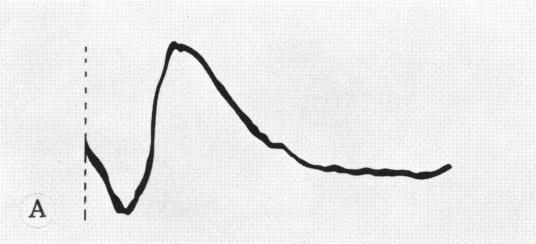

Systemic immunization with purified homologous rhodopsin from retinal outer segments induced blindness in primates (Macaca mulatta). Inflammation and characteristic retinal changes were the earliest clinical signs of the disease. Perivasculitis, subretinal exudations and bullous detachments of the retina were progressive and unrelenting pathological processes leading to rapid and irreversible visual deterioration. Electroretinographic responses (ERG) at this stage of the disorder became abolished. Antibodies and delayed hypersensitivity to rhodopsin were demonstrated only in the experimental diseased animals. Homologous visual purple appears to be organ and immunopathologically specific. Histological confirmation of these findings showed a pathological spectrum of destructive alterations confirmed specifically to the outer segments of the entire retina. The pathologic reaction was supported by a distinct and pronounced granulomatous inflammatory response.